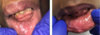

What is this infectious disease?

What probably this patient also have?

HSV1: primary herpetic gingivostomatitis

there are multiple irregularly shaped

ulcers present on the fixed and movable mucosa –> most likely

diagnosis is primary herpetic gingivostomatitis since the patient has

fever and malaise.